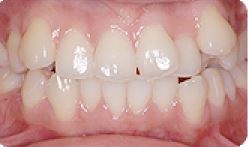

치아교정 자가결찰브라켓 전후사례 | 2020.03.06 |